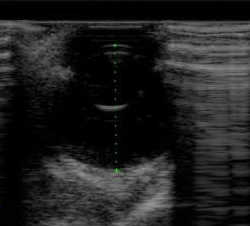

目にエコー検査できるの?

目 超音波

超音波診断装置(エコー)により目の奥を画像診断します。

超音波を目に当てて、虹彩、網様体、水晶体、網膜等の構造を検査します。エコー検査により、網膜剥離や白内障、腫瘍の有無等が評価できます。